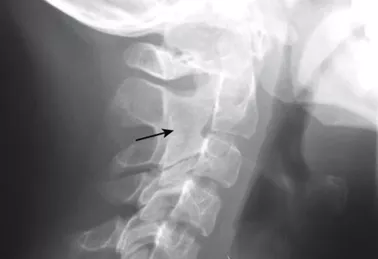

Фото 7. Ретрогнатия у 12-летней пациентки с РФ-негативным полиартикулярным ЮИА (дебют ЮИА был в 3 года) [9]. Фото 8. Боковая рентгенограмма шейного отдела позвоночника ребенка с РФ-негативным ЮИА, показывающая костный анкилоз второго и третьего шейных позвонков [9].

Инструментальные исследования: Рентгенологическое исследование. Определяется сужение суставных щелей. Через 2 года от дебюта заболевания анкилоз в суставах запястья развивается у 12% пациентов, через 6 лет — у 43%. На поздних стадиях анкилоз возникает в апофизальных суставах II и III шейных позвонков.

Рентгенография суставов: сужение суставных щелей и эрозии кости в лучезапястных суставах, мелких суставах кистей, стоп и плечевых суставах появляются в течение первых двух лет течения болезни. В костях запястья разрушение хряща происходит в проксимальном запястном суставе и интеркарпальных суставах, что приводит к карпальному анкилозу и укорочению конечности (фото 12). Также часто развивается атланто-аксиальное переразгибание.